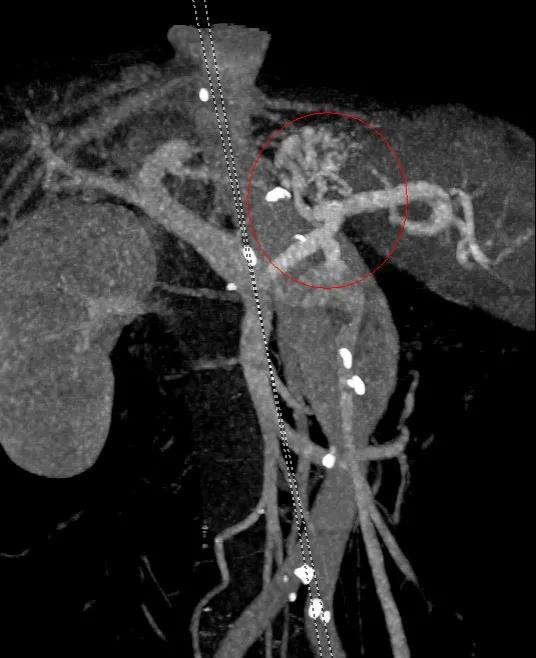

入院后予禁食、抑酸、補液、輸血處理,與家屬溝通,完善胃鏡檢查,結果示胃底巨大曲張靜脈團、門脈高壓性胃病。蓋偉主任考慮胃底靜脈團大、靜脈壓力高,合并分流道的可能性越大,且多數為胃脾分流,應首先完善門靜脈血管成像檢查,以明確血管情況。成像檢查結果符合食管胃底靜脈曲張CT表現,胃底血管部分與脾靜脈相交通。

科室組織術前討論,共同讀片,分析:該患者巨大胃底靜脈曲張存在胃脾分流道,巨大者難以套扎,常規組織膠血管內注射治療易引起異位栓塞。術前CT門脈成像檢查清晰顯示靜脈團的血管走行及血管的出入口大致在胃底的位置,鈦夾夾閉可以先行阻斷或減緩血流,隨后的組織膠治療不易發生異位栓塞。于是,團隊決定采用目前最新的鈦夾限流聯合組織膠栓塞術處理該患者的胃底曲張靜脈。

術前胃鏡及血管成像